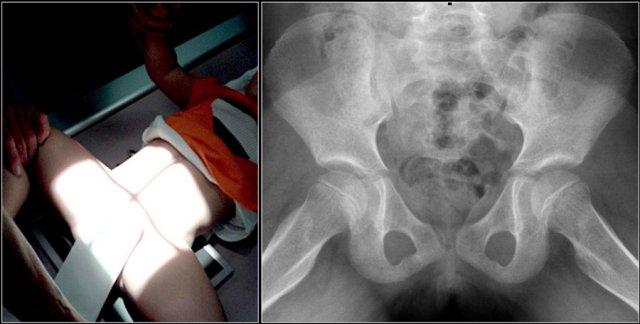

Trượt đầu xương đùi ở một bé trai mười ba tuổi. Phim X-quang tư thế thẳng cho thấy đầu xương hơi rộng, nhưng dấu hiệu này dễ bị bỏ sót. Tư thế chụp nghiêng kiểu ếch cho thấy trượt đầu xương đùi trái ra sau-trong.

Trượt đầu xương đùi (SCFE) hay còn gọi là tiêu xương đùi đầu là gãy xương Salter-Harris type I vô căn của đầu xương đùi gần.

Bệnh gặp nhiều hơn ở trẻ trai và trẻ béo phì. Độ tuổi biểu hiện điển hình là từ 12 đến 15 tuổi.

Đầu xương trượt ra sau, và ở mức độ ít hơn là vào trong.

Do đó, dấu hiệu này được đánh giá tốt nhất trên tư thế chụp nghiêng kiểu ếch.

SCFE được điều trị bằng cố định phẫu thuật để ngăn ngừa trượt thêm.